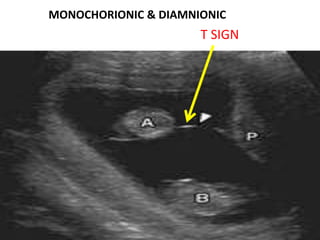

MONOCHORIONIC & DIAMNIONIC

T SIGN